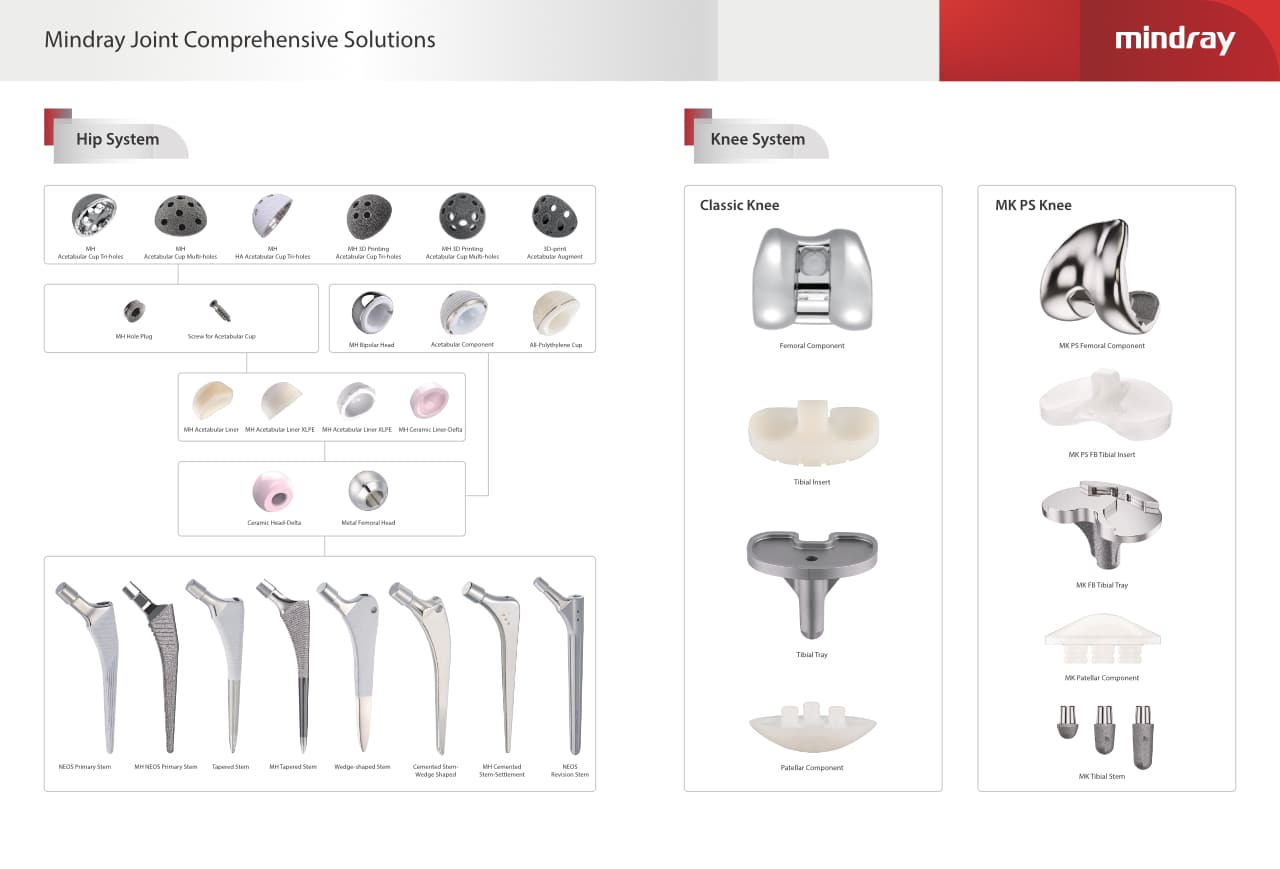

РһСҖСӮРҫРҝРөРҙРёСҮРөСҒРәРҫРө РҝРҫРҙСҖазРҙРөР»РөРҪРёРө РәРҫРјРҝР°РҪРёРё Mindray, СҖР°СҒРҝРҫР»РҫР¶РөРҪРҪРҫРө РІ РЈС…Р°РҪРө, СҸРІР»СҸРөСӮСҒСҸ РҫРҙРҪРёРј РёР· РІРөРҙСғСүРёС… РҝСҖРҫРёР·РІРҫРҙРёСӮРөР»РөР№ РҫСҖСӮРҫРҝРөРҙРёСҮРөСҒРәРҫР№ РҝСҖРҫРҙСғРәСҶРёРё РёР· РҡРёСӮР°СҸ. РһРҪРҫ Р·Р°РҪРёРјР°РөСӮСҒСҸ РёСҒСҒР»РөРҙРҫРІР°РҪРёСҸРјРё Рё СҖазСҖР°РұРҫСӮРәРҫР№, РҝСҖРҫРёР·РІРҫРҙСҒСӮРІРҫРј Рё РјР°СҖРәРөСӮРёРҪРіРҫРј СӮСҖавмаСӮРҫР»РҫРіРёСҮРөСҒРәРёС… Рё СҒРҝРёРҪалСҢРҪСӢС… РёР·РҙРөлий, РҝСҖРҫРҙСғРәСҶРёРё РҙР»СҸ Р°СҖСӮСҖРҫРҝлаСҒСӮРёРәРё Рё РҙСҖСғРіРёС… С…РёСҖСғСҖРіРёСҮРөСҒРәРёС… РёР·РҙРөлий. РЎ РјРҫРјРөРҪСӮР° СҒРІРҫРөРіРҫ РҫСҒРҪРҫРІР°РҪРёСҸ РІ 1999 РіРҫРҙСғ РјСӢ СғСҒРҝРөСҲРҪРҫ РҝСҖРҫСҲли СҒРөСҖСӮифиРәР°СҶРёСҺ ISO 9001, ISO 13485 Рё CE, РІСӢРҙР°РҪРҪСғСҺ T?V Рё СҚРәСҒРҝРҫСҖСӮРёСҖСғРөРј РҝСҖРҫРҙСғРәСҶРёСҺ РІ РұРҫР»РөРө СҮРөРј 50 СҒСӮСҖР°РҪ РҝРҫ РІСҒРөРјСғ РјРёСҖСғ.